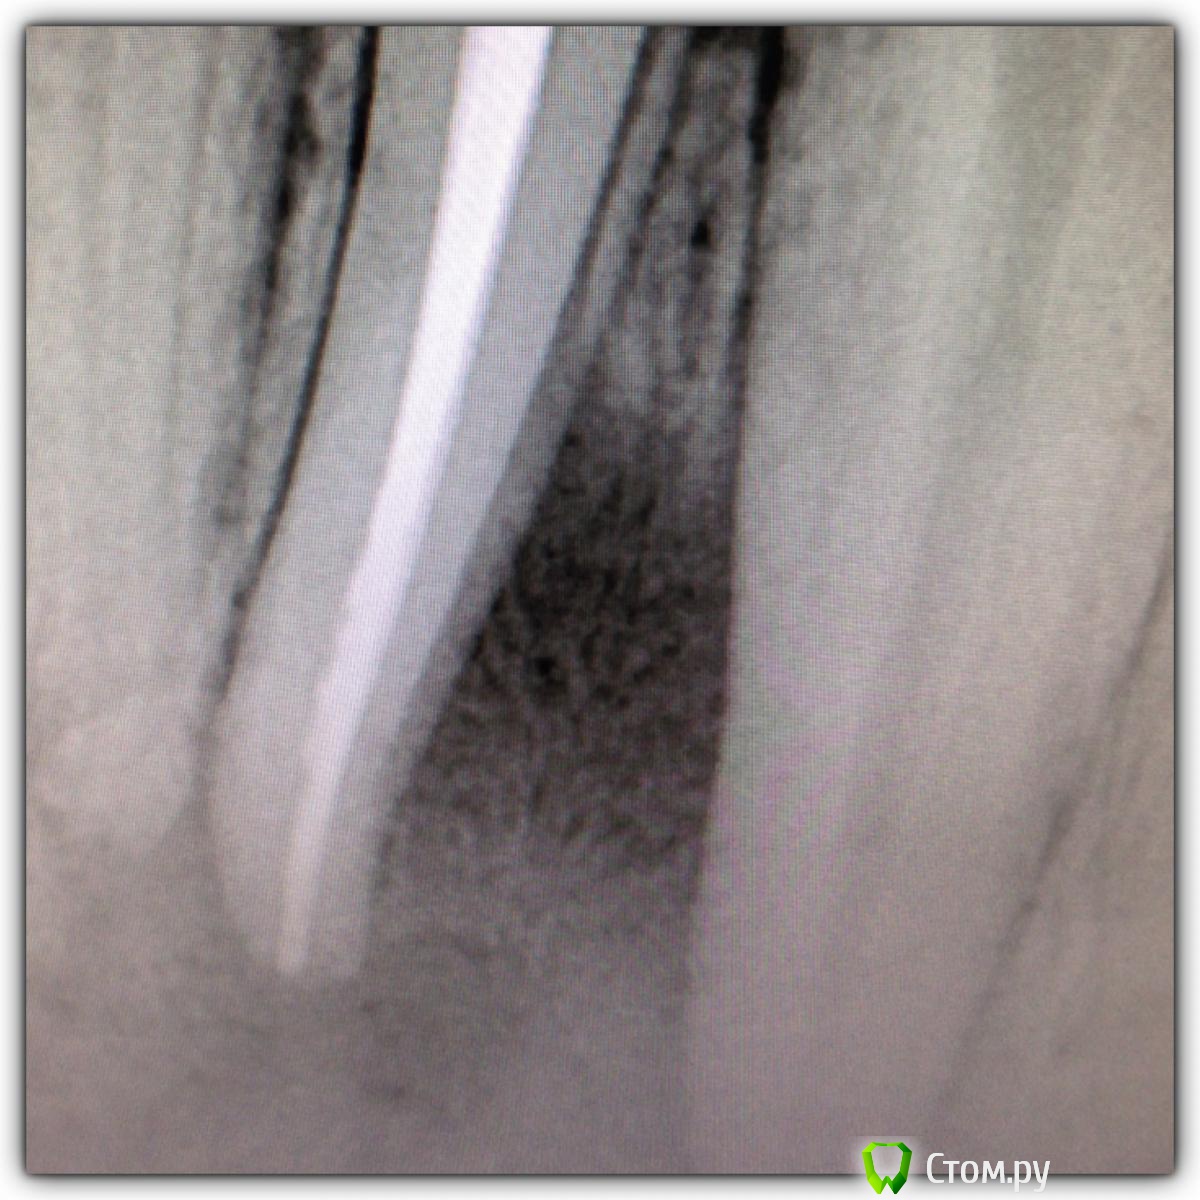

SSTi Опубликовано 15 октября, 2014 Автор Поделиться Опубликовано 15 октября, 2014 Продолжение истории сообщения 107. Прошло 5 месяцев. Пациент забежал сегодня записаться. Заодно сфоткались. Углы разные. И верхняя единица. Что думаете? 7 Ссылка на комментарий

SSTi Опубликовано 16 октября, 2014 Автор Поделиться Опубликовано 16 октября, 2014 46. Пульпит. По приказу свыше. Убрал бломбу, каривус. Коффер. Открываемся. Полость склерозирована. В ней- дентикль. Уз убрал. В каналы только десятка заходит. Долго долго расширял. Очень долго. Дистальные 25.06, 30.04 профайл. Медиальные 20.06, 25.04. Ирригация стандартная. И очень обильная. Дистальные сходится. П.с. Про кость знаю. 5 Ссылка на комментарий